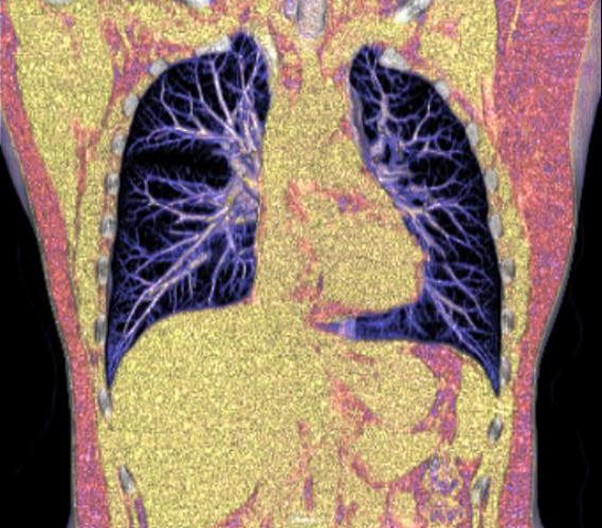

臨床畫(huà)廊